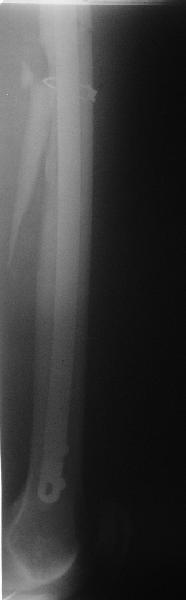

фото несращения бедра

Имя     : фото 3.jpe